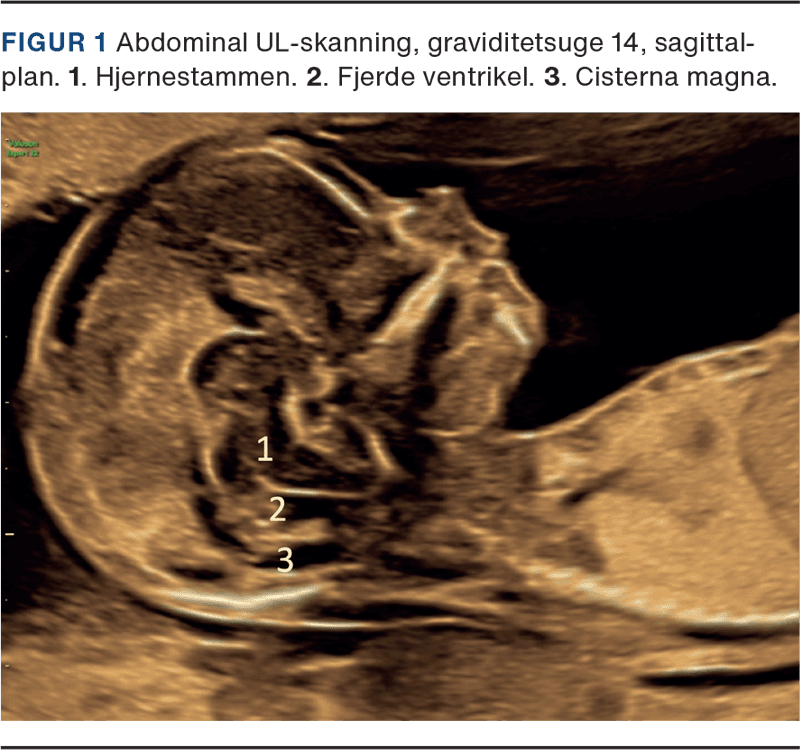

UL-skanning i 1. trimester foretages i graviditetsuge 11-14 og udføres som udgangspunkt med 2D-abdominalskanning. Ved behov kan der suppleres med vaginalskanning og evt. 3D-skanning. CNS vurderes i et midt-sagittalt og aksialt plan, hvor følgende visualiseres: intakte kranieknogler med henblik på at udelukke akrani og store encefaloceler, midtlinie og symmetriske hemisfærer og lateralventriklerne udfyldt af plexus choroideus. Der måles biparietaldiameter for at sikre intakt kranium og overensstemmelse mellem crown-rump-length og caputs størrelse. Columnas udseende og form vurderes for at udelukke alvorlig columnadefekt [5, 6]. Ud over de strukturer, der er obligatoriske at fremstille ved rutineundersøgelsen, kan man nu ofte allerede i 1. trimester visualisere thalamus, cerebrale pedunkler, aquaductus cerebri, plexus choroideus, hjernestammen, cisterna magna og tredje og fjerde ventrikel (Figur 1 og Figur 2) [5].

Der er høje detektionsrater for en række alvorlige neuralrørsdefekter i 1. trimester: akrani: 98%, holoprosencefali: 88-92%, encefalocele: 89-95% og åben spina bifida: 68% [6, 7]. For at opnå høje detektionsrater er en systematisk undersøgelsesprotokol afgørende.